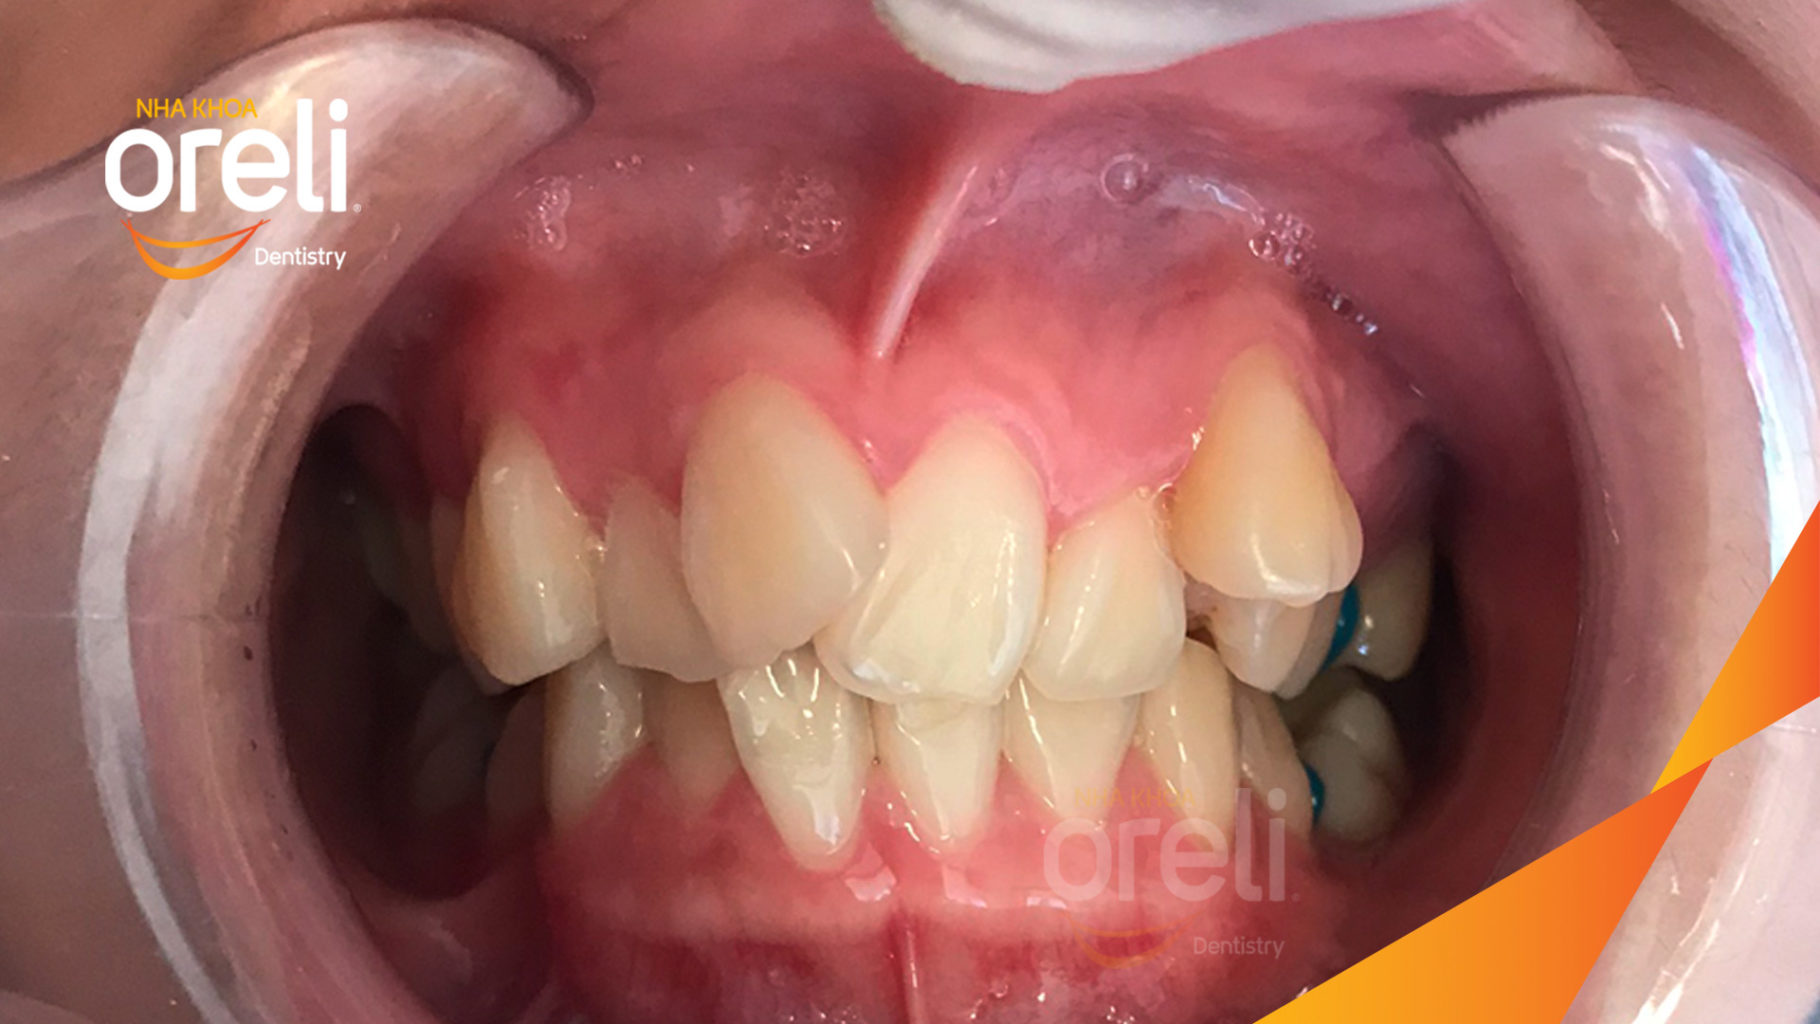

Ca niềng chỉnh chen chúc hẹp hàm nặng cả trên và dưới – Kết quả điều trị thực tế tại nha khoa Oreli

Ca niềng răng chen chúc phục hồi ăn nhai và thẩm mỹ nụ cười. Kết quả thực tế trước và sau điều trị tại Nha khoa Oreli.

Hình ảnh thực tế